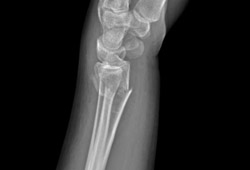

- radiografias simples do punho

- tomografia computadorizada (TC) do punho